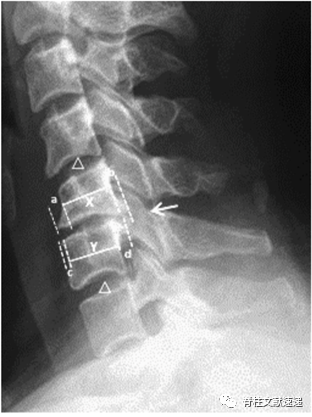

1.局灶型项韧带骨化的位置往往位于椎管最狭窄的水平;

2. 局灶型项韧带骨化的位置与椎体骨赘的大小有关;

3. 局灶型项韧带骨化的位置与椎间盘退变的程度有关。如下图所示:C5/6颈椎不稳、骨质增生,项韧带骨化发生于C5和C6棘突之间。